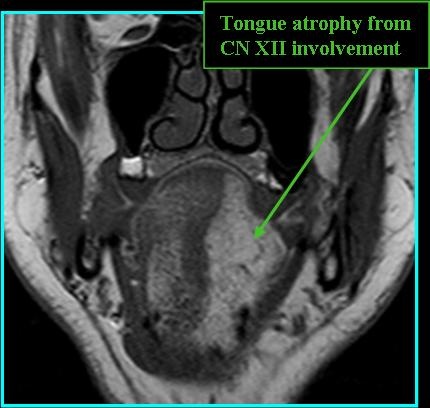

- Can arise from three distinct locations: the jugular bulb, the tympanic branch of CN IX, or the auricular branch of CN X

- Symptoms may include pulsatile tinnitus, hearing loss, dysphonia, shoulder weakness/pain, dysarthria, facial paralysis (Moore et al. 2016)